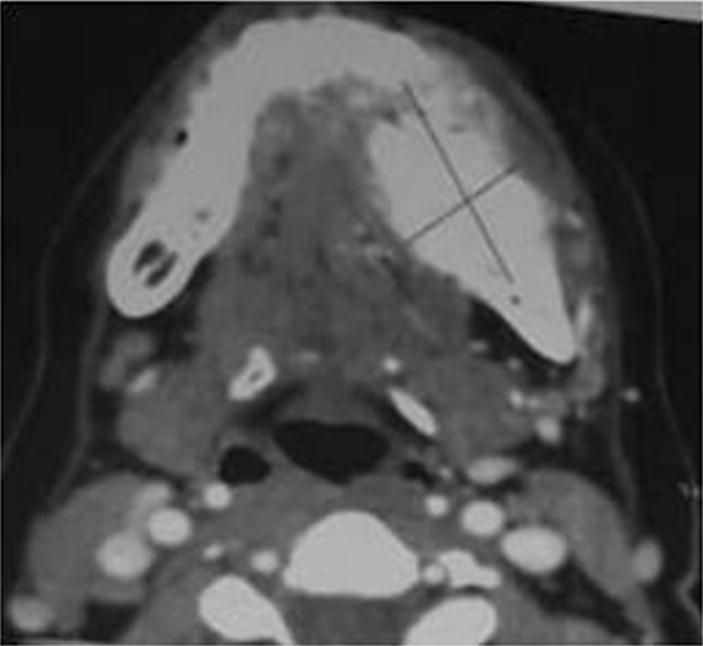

An orthopantomogram (OPG) showed radiopaque mass measuring about 3x3 cm in left body of mandible showing classical sun burst appearance (Fig. 2). 3D MDCT scan showed large bony mass lesion involving left body of the mandible measuring 41.8 mm × 25.4 mm with osteoid bone matrix and adjacent periosteal reaction (Fig. 3). Axial view CT scan confirmed the clinical finding of lingual cortical expansion (Fig. 4). Clinical and radiographic features were strongly suggestive of osteosarcoma of body of mandible. Routine haematological investigations were done. An open biopsy was performed with direct incision over the bone in the representative region; adequate size of bone tissue was removed using straight hand piece and copious saline irrigation. Continuous oozing was observed from the lesion obscuring the field. Incisional biopsy was also obtained from overlying soft tissues. Haemostasis was achieved by using local haemostatic measures. Samples were sent for histopathological examination which on H and E stained section showed osteoid material with atypical osteocytes, at focal areas chondroblastic tissues with atypical cells were evident while few sections showed cellular areas blending into malignant osteoid tissues confirming the diagnosis of OS of body of mandible (Fig. 5). The soft tissue biopsy was inconclusive. Patient was then referred to oncology department for further management. There she underwent hemi-mandibulectomy with disarticulation followed by free fibula microvascular reconstruction and followed by adjuvant chemotherapy. Final diagnosis of osteosarcoma of body of mandible with a skip metastastatic lesion in mandibular condyle was confirmed from histopathology reports.

Fig. 4.

MDCT axial view showing lingual cortical expansion

Radiological feature is of utmost importance as it acts as guide for the pathologist to correlate with clinic-pathological findings. Radiographic attributes include widening of periodontal ligament space along with the enfeeblement of lamina dura around a jaw tumour [6, 7]. However our patient had previous history of extraction of tooth in the same region, so the latter finding was truant. Radiographic appearance is based on the histological changes present in particular stage of osteosarcoma. It may display either bone formation (osteogenic), bone destruction (osteolytic) or a combination of both. Our patient’s OPG showed diffuse radiopacity in left body of mandible similar to that of classic “sun burst” appearance of osteosarcoma indicating malignant changes in the process of osteoid formation. Though OPG acts as a chaperon in the differential diagnosis, it has its own pitfalls such as image distortion and magnification. CT scan or MRI scan can be used as an advanced diagnostic tool to conclude on a more definitive diagnosis. The CT scan of our patient clearly delineated periosteal reaction with bony expansile lesion and osteoid bone matrix showing strong proclivity towards OS.